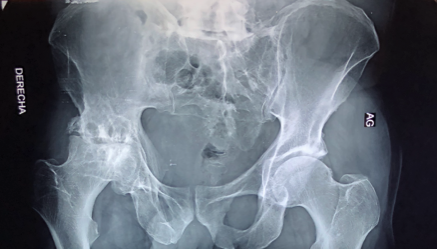

The femoral head and hip joint were quite degenerated making mobility difficult and very painful for Oscar.

The femoral head on Oscar's right hip is very degenerated.